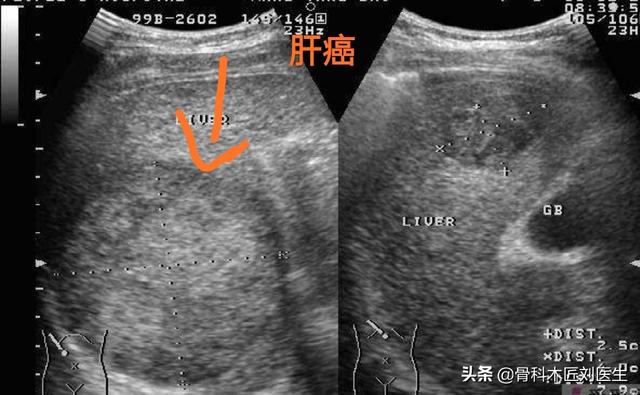

- まず、肝がんのスクリーニングには、超音波検査で1cm以上の肝腫瘍をはっきり検出できることと、肝がんの腫瘍マーカーであるα-フェトプロテインが肝がんの診断精度を強力に高めることから、超音波検査とα-フェトプロテインを組み合わせた検査をお勧めします。 この2つの検査の組み合わせは、精度も高く、費用も抑えられるので、費用対効果は非常に高いです。

- 肝臓の超音波検査で肝臓に腫瘍が見つからない場合、または腫瘍の性質が判断できない場合、αフェト蛋白の上昇は肝細胞癌の可能性を強く疑わせる。さらに肝臓のCTを行うこともある。強化CTは肝臓腫瘍の特定に比較的優れているので、すぐに肝臓の強化CTをお勧めします。